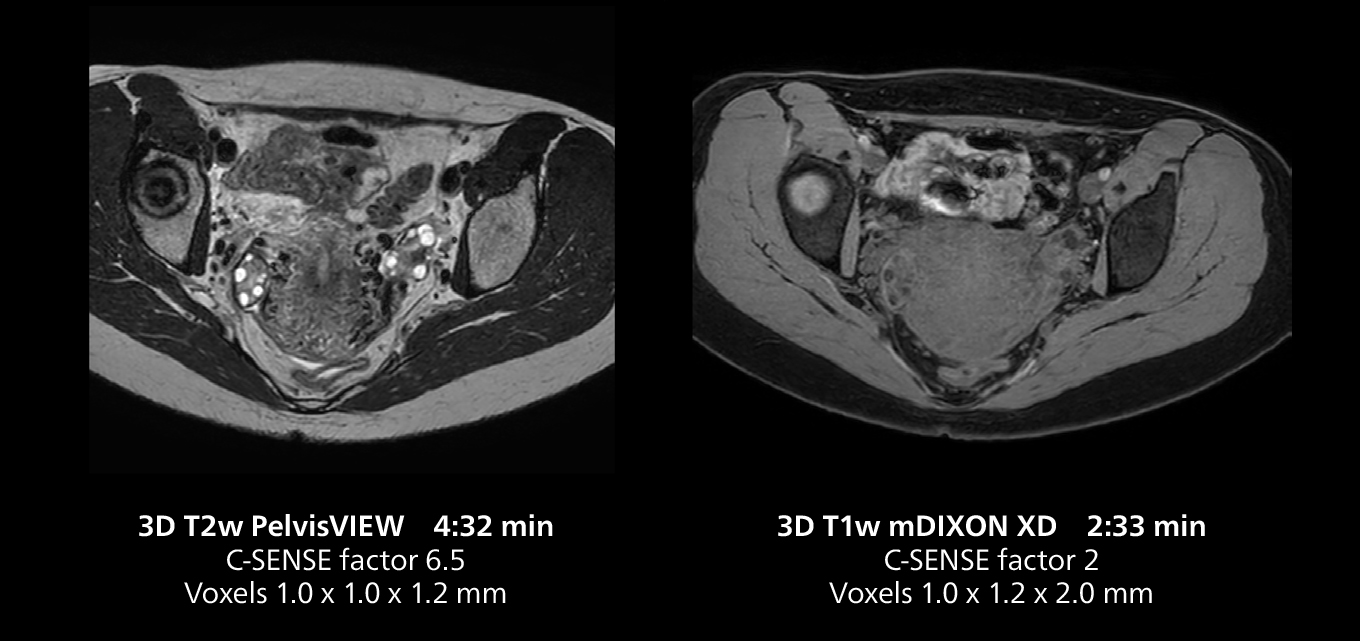

This MRI case illustrates good resolution and imaging quality obtained within reasonable scan times using the MR 5300 1.5T system with the anterior torso cardiac coil that allows use of a large field of view (FOV).

Dr. Gellée highlights the robust free-breathing scans as “the feature that makes the biggest difference in my daily work. The 3D free breathing sequences are very reproducible, and the axial acquisition is very good. For example, in endometriosis, which is one of my focus areas, it provides high contrast and good resolution so that I can see small details. We also use free breathing for liver and pancreas imaging. In multi-phase liver studies, 4D Free Breathing delivers 3-second temporal resolution, making a dynamic scan with more than one arterial phase possible.”

The MR 5300 with Compressed SENSE is up to 50%** faster for many exams. It can provide routine exams in less than 5 minutes and whole-body exams in less than 20 minutes. Saint-Augustin has taken advantage of that speed to create highly efficient protocols. The hospital’s standard stroke protocol is just about 8 minutes, and standard ENT, prostate PIRADS staging, and endometriosis studies all clock in at just about 10 minutes.***

“We have more speed in 3D sequences,” Dr. Gellée states. “With Compressed SENSE, we can replace two or three 2D scans withone high-quality 3D scan. High quality additional orientations are then obtained by post-processing of the 3D data set, thus saving scanning time.”